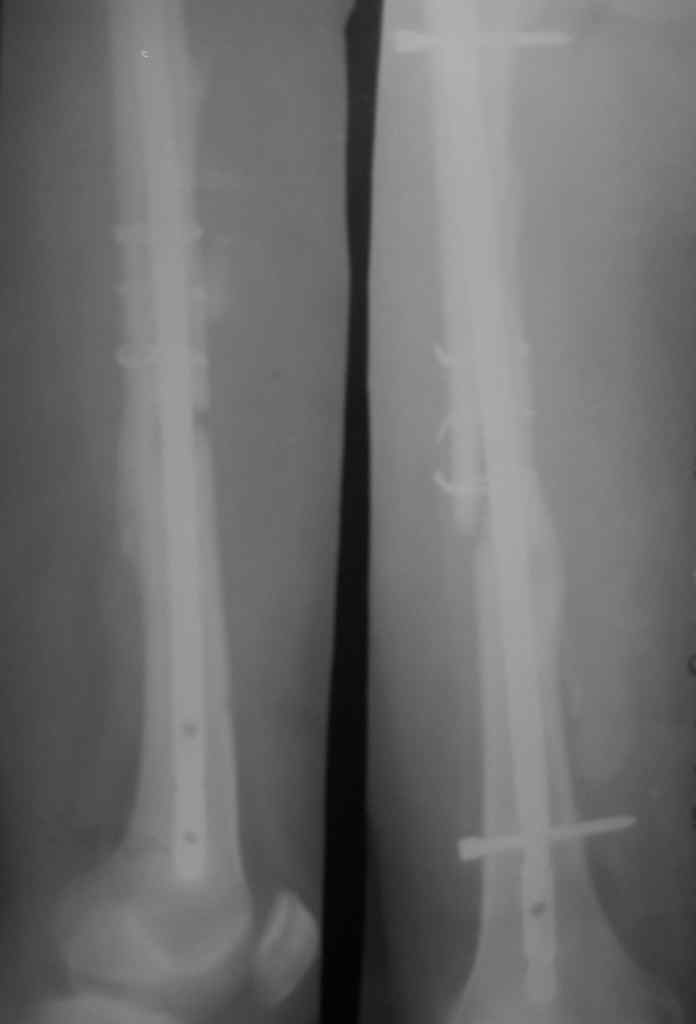

Перелом стержня, серкляж

Поступила молодая,маленькая девочка 18 лет с болями в левом бедре. Из истории:автодорожная травма в ноябре 2005 года, тогда же оперировалась данным способом. Проживает в селе и как правило в таких случаях выпала из поля зрения ведущего доктора.

Ноябрь 2005г. и 18 лет это не 6-8мес это год. на последних снимках разве мы видим элементы "ЗДОРОВОЙ" консолидации сдесь должна быть серьезная гипертрофическая мазоль.

на мой взгляд, выбирать конечно Вам. необходимо удалить стержень, убрать серкляжи под которыми Вы увидите "проблемную" кость. обязательно произвести костную аутопластику "вязанкой хвороста" дать компрессию предварительно заблокировав дистально в двух плоскостях и хорошую остеотропную терапию, раннюю нагрузку. и обследуйте больную на маркеры регенерации. Стержень длинноват и винты бы покороче. С Уважением Куликов.